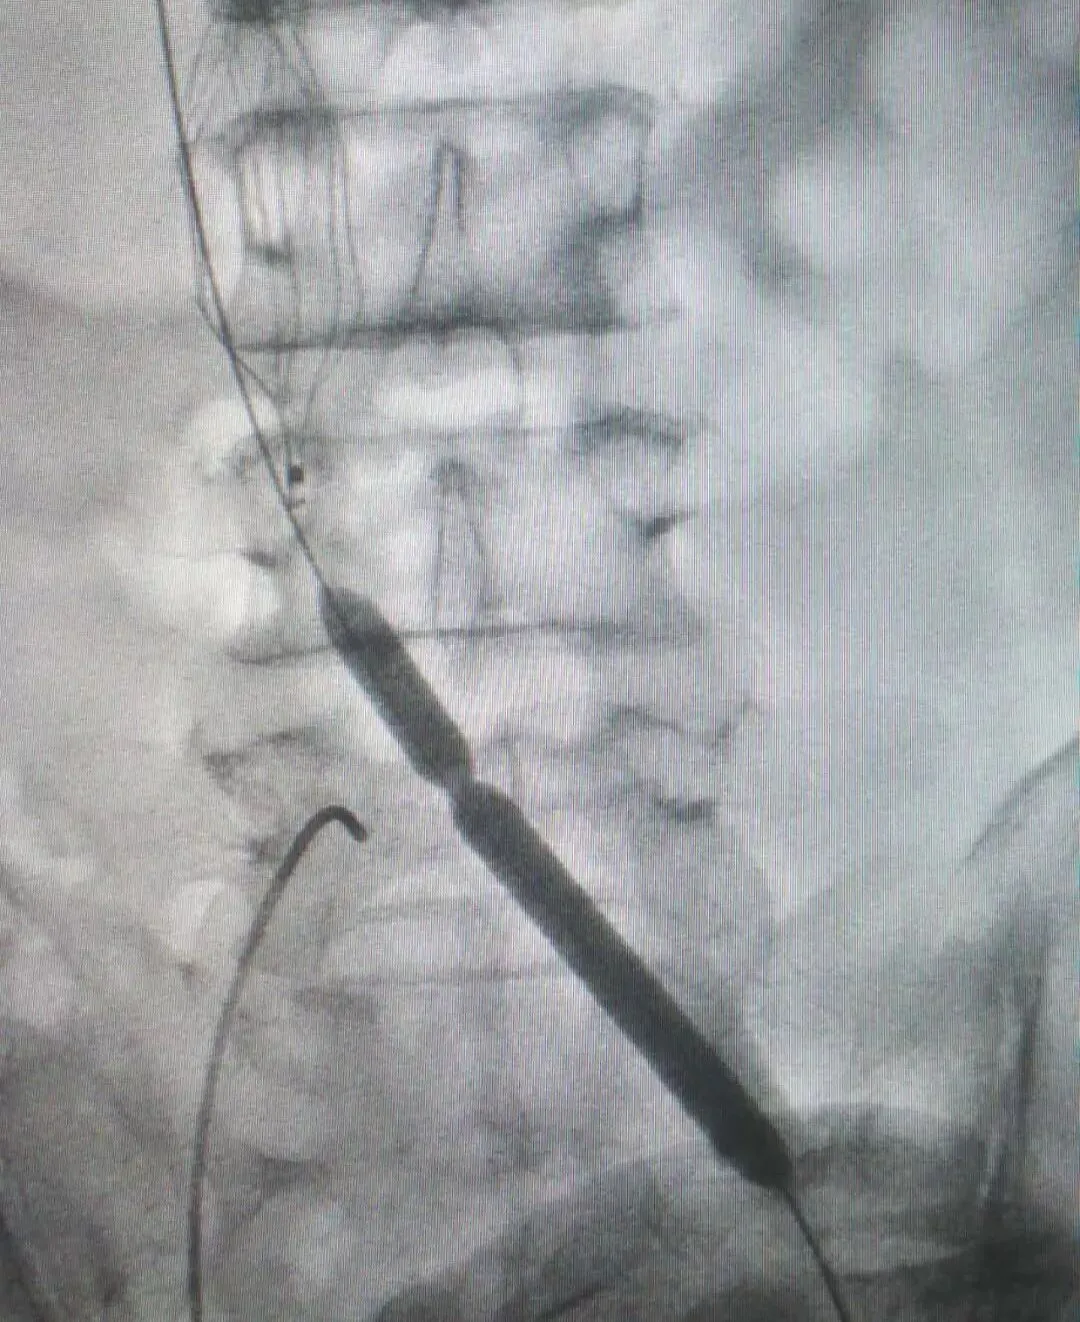

术中造影显示,王大叔左侧股静脉、髂总静脉有长段血栓形成,阻塞范围约有30cm长。由于静脉的血管壁薄,血管闭塞时间长,病变范围广,所以手术的风险极高。丛海波院长和影像科主任兼介入、血管外科负责人侯红军团队决定为其进行“左股静脉切开取栓+左髂总静脉闭塞球囊扩张术”,术中用取栓导管取出40-50毫升血栓,由于髂总静脉开口处血管质地硬,导管无法直接通过,采用导丝导管技术通过了闭塞段,并用球囊逐级扩张。

(球囊扩张过程)